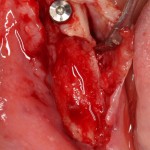

В этом случае остеопластика делается отдельной процедурой. Ее принципы точно те же, но уже без импланта. Например:

Имплантировать в таких условиях — заведомо обрекать себя на хреновый, с точки зрения эстетики и функциональности, результат. Поэтому первым этапом проводим остеопластику. Объем небольшой, использовать в таких объемах костный блок не очень рационально. Воспользуемся аутокостной стружкой и мембраной.

Сначала фиксируется BioGide. Это легко:

Затем укладывается и конфигурируется аутокостная стружка:

Если после этого BioGide намочить физраствором, им легко укрыть получившийся объем:

Для надежности можно зафиксировать пинами:

Ну и, швы: